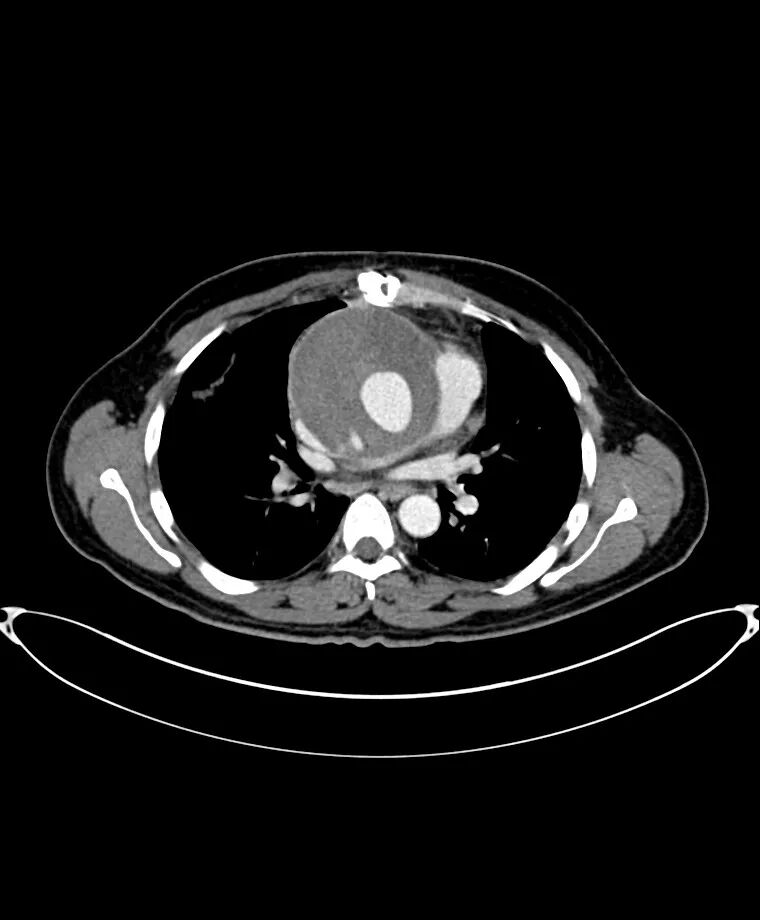

斯坦福a型主动脉夹层

图片尺寸760x920